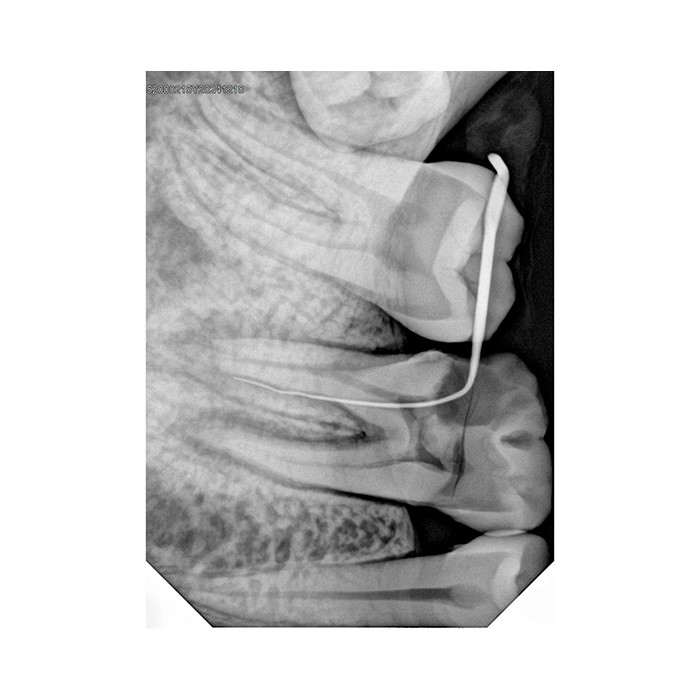

Области применения

Handy HDR-380 незаменим для широкого спектра диагностических задач в терапевтической, хирургической, ортопедической и ортодонтической стоматологии. С его помощью вы сможете выполнять прицельные внутриротовые снимки для оценки состояния отдельных зубов, пародонта, контроля качества пломбирования каналов и установки имплантатов.